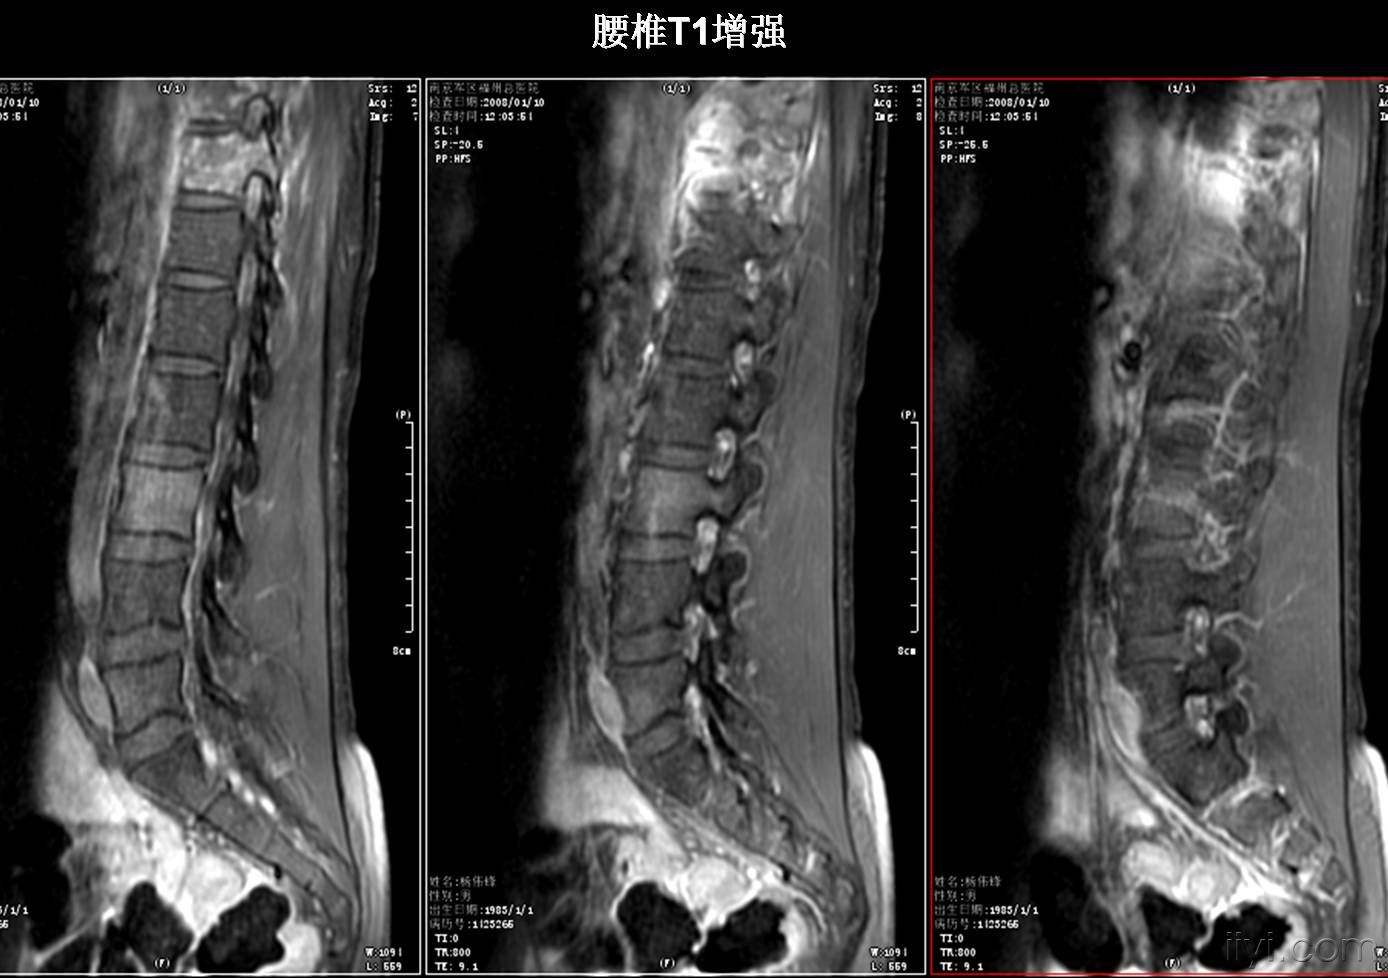

MR则善于在软组织里“找不同”,可以清楚地分辨肌肉、肌腱、筋膜、脂肪等软组织,区分膝关节的半月板、交叉韧带、关节软骨等,子宫的肌层、子宫内膜层,前列腺的肌肉层与腺体层,心脏的心内膜、心肌和心外膜以及外层的心包,因此,对于关节、脊髓、前列腺、膀胱、子宫、卵巢、心脏大血管病变及心肌梗塞的诊断尤为准确。

对比于CT只能水平“切割”,MR则有“横切”、“竖切”等任意方向切层成像的本事,全面显示被检查器官或组织的结构,无视死角,还可以通过计算机组合出一个三维立体图像,方便医生进行解剖结构或病变的立体观察。

对于脑梗塞,MR可以轻易分辨坏死脑组织和健康脑组织,即使是梗塞早期,CT看不出任何变化时,它都能清楚显示,因此是早期诊断的重要依据。另外,对于诊断脑肿瘤、颅内动脉瘤、动静脉血管畸形等颅脑常见疾病非常有效,同时对腰椎椎间盘后突、原发性肝癌等疾病的诊断率也很高。